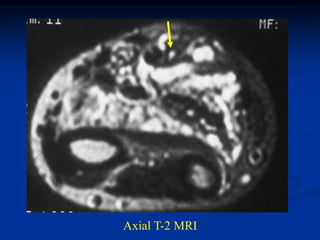

Case #1185

59 year female with

intramuscular lipoma

anterior proximal thigh

Coronal T-1 MRI

Axial T-2 MRI

at lower level

Fat subtraction MRI

showing signal void

in lipoma

Case #1185 59 yearfemale with intramuscular lipoma anterior proximal thigh Coronal T-1 MRI

• 54.

• 55.

Axial T-2 MRI atlower level

• 56.

Fat subtraction MRI showingsignal void in lipoma